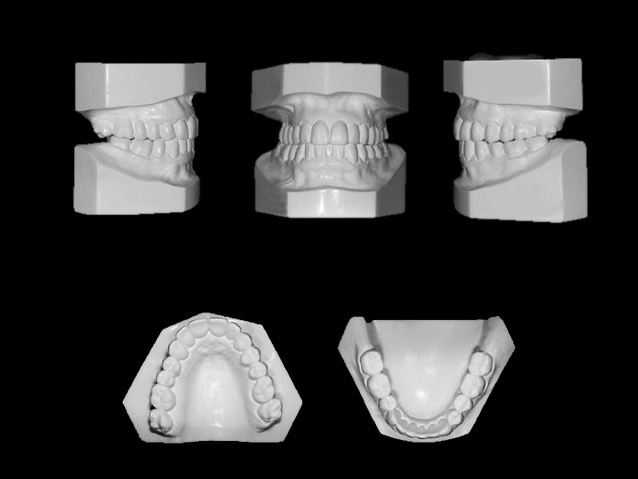

Ofrecemos la más alta tecnología con una atención profesional y personalizada por parte del equipo altamente calificado en donde contará con el mejor estudio para sus pacientes.